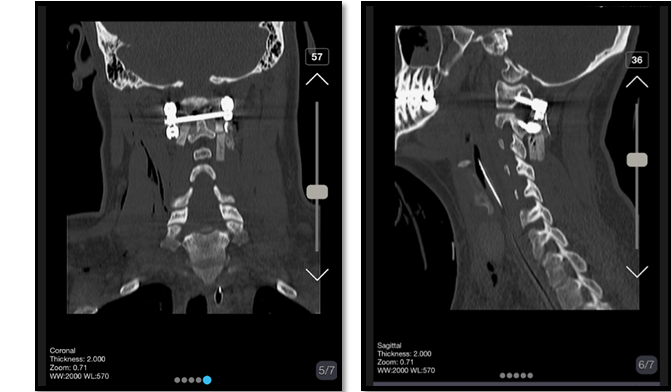

A 23-year-old Iranian gentleman was admitted to Shahid-Beheshti Hospital of Kashan and was hit by a Motor-to-Barrier Accident. He was fully conscious and oriented with a normal level of consciousness and was treated according to the Advanced Trauma Life Support Protocol. He was hemodynamically stable and experiencing mild respiratory distress due to cervical edema and tenderness. On examination, he had cervical tenderness (C1-C2) and a GCS of 15/15, pupils were symmetrical and reactive to light, and movement was normal in four extremities. There was no swelling or laceration in the scalp; however, tenderness in the neck was detected. The physical examination showed no neurological deficits, neither motor nor sensory. He had cervical motion and rotation limitations. His Deep tendon Reflexes were normal. A CT scan revealed a posterior subluxation of the odontoid process lay in front of the atlas anterior arch with no associated fractures and disruption of the spinolaminar line (Figure-1). No intracranial hemorrhage or midline shift was seen.

Figure 1. Pre-operative cervical CT scan shows posterior subluxation of the odontoid process lying in front of the anterior arch of the atlas, with no associated fractures or disruption of the spinolaminar line.